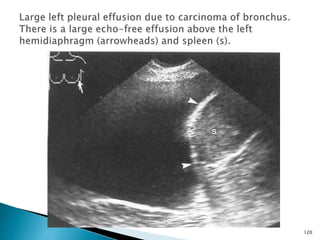

ULTRASONOGRAPHY

 Ultrasound scanning provides a radiation-

free access to certain types of

bronchogenic carcinoma.

 This is particularly true for Pancoast

tumours which occur at the lung apex and

can be viewed from the supraclavicular

fossa.

 Ultrasonography can also be used to

evaluate large pleural effusions in cases

where a mass is suspected.